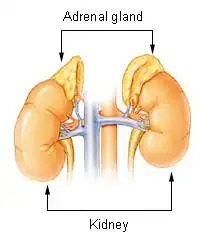

Adrenalism describes the condition of an excessive or substandard secretion of hormones related to the adrenal glands, which are found directly superior to the kidneys.[1][2] Adrenalism can be further distinguished as hyperadrenalism, referring to the excessive secretion of hormones, and hypoadrenalism, referring to the insufficient secretion of hormones.[3][4]